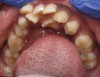

Bruxism commonly accompanies airway obstructions in children. DiFrancesco and colleagues evaluated 69 consecutive children who presented to the Otolaryngology Department of the University of São Paulo Medical School for tonsil and adenoid removal.3 Before surgery, the children's parents reported that 100% experienced sleep apnea, 45.6% engaged in bruxism, and 60.7% possessed dental malocclusions. Three months after surgery, none of the children presented with breathing problems, and 11.8% presented with bruxism. Because there was a significant improvement in bruxism after surgery, the study data suggests that there is a positive correlation between sleep-disordered breathing and bruxism. The researchers conclude that otolaryngologists must be aware that bruxism is associated with airway obstruction and consider it when evaluating tonsil and adenoid hyperplasia (Figure 4 and Figure 5).

(4.) Enlarged tonsils and adenoids are commonly accompanied by bruxism. Figure 5 courtesy of Kevin Boyd, DDS, MSc.

Figure 4

(5.) Enlarged tonsils and adenoids are commonly accompanied by bruxism. Figure 5 courtesy of Kevin Boyd, DDS, MSc.

Figure 5